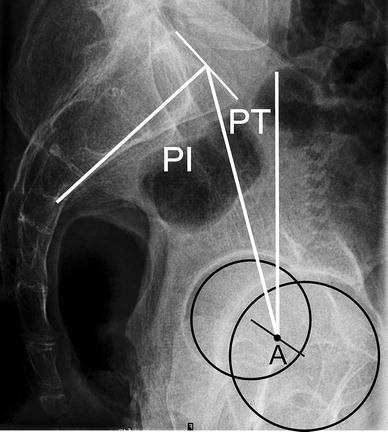

MEDIDAS SPINE

MEDIDAS PELVE